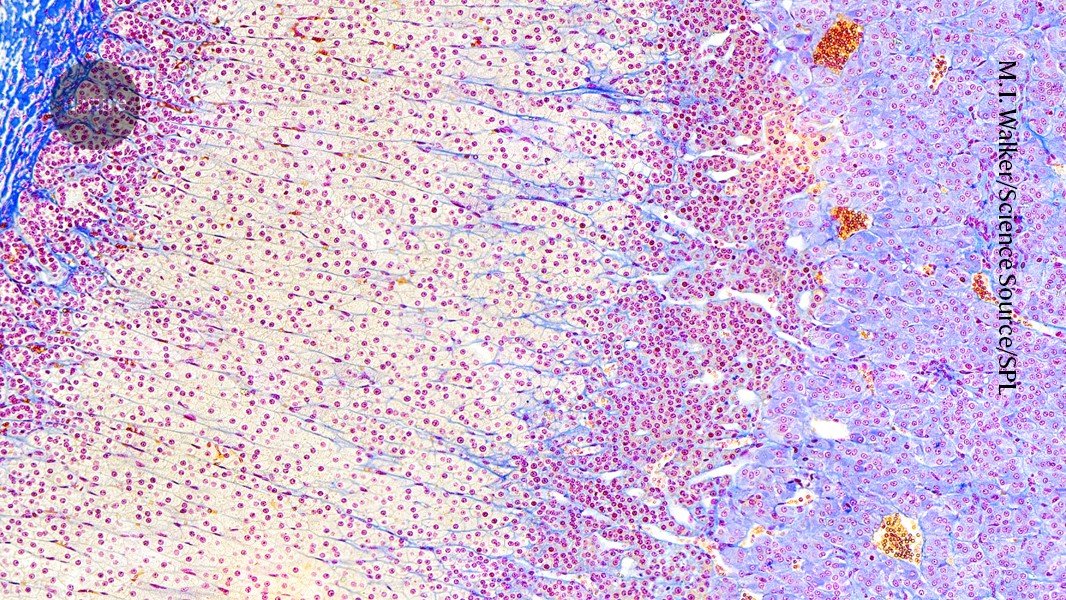

Newly developed organoids perform some of the functions of the adrenal gland (pictured), which secrete a variety of hormones. Credit: M. I. Walker/Science Source/Science Photo Library

Lab-grown structure mimics the adrenal cortex, which produces the critical hormone called cortisol.